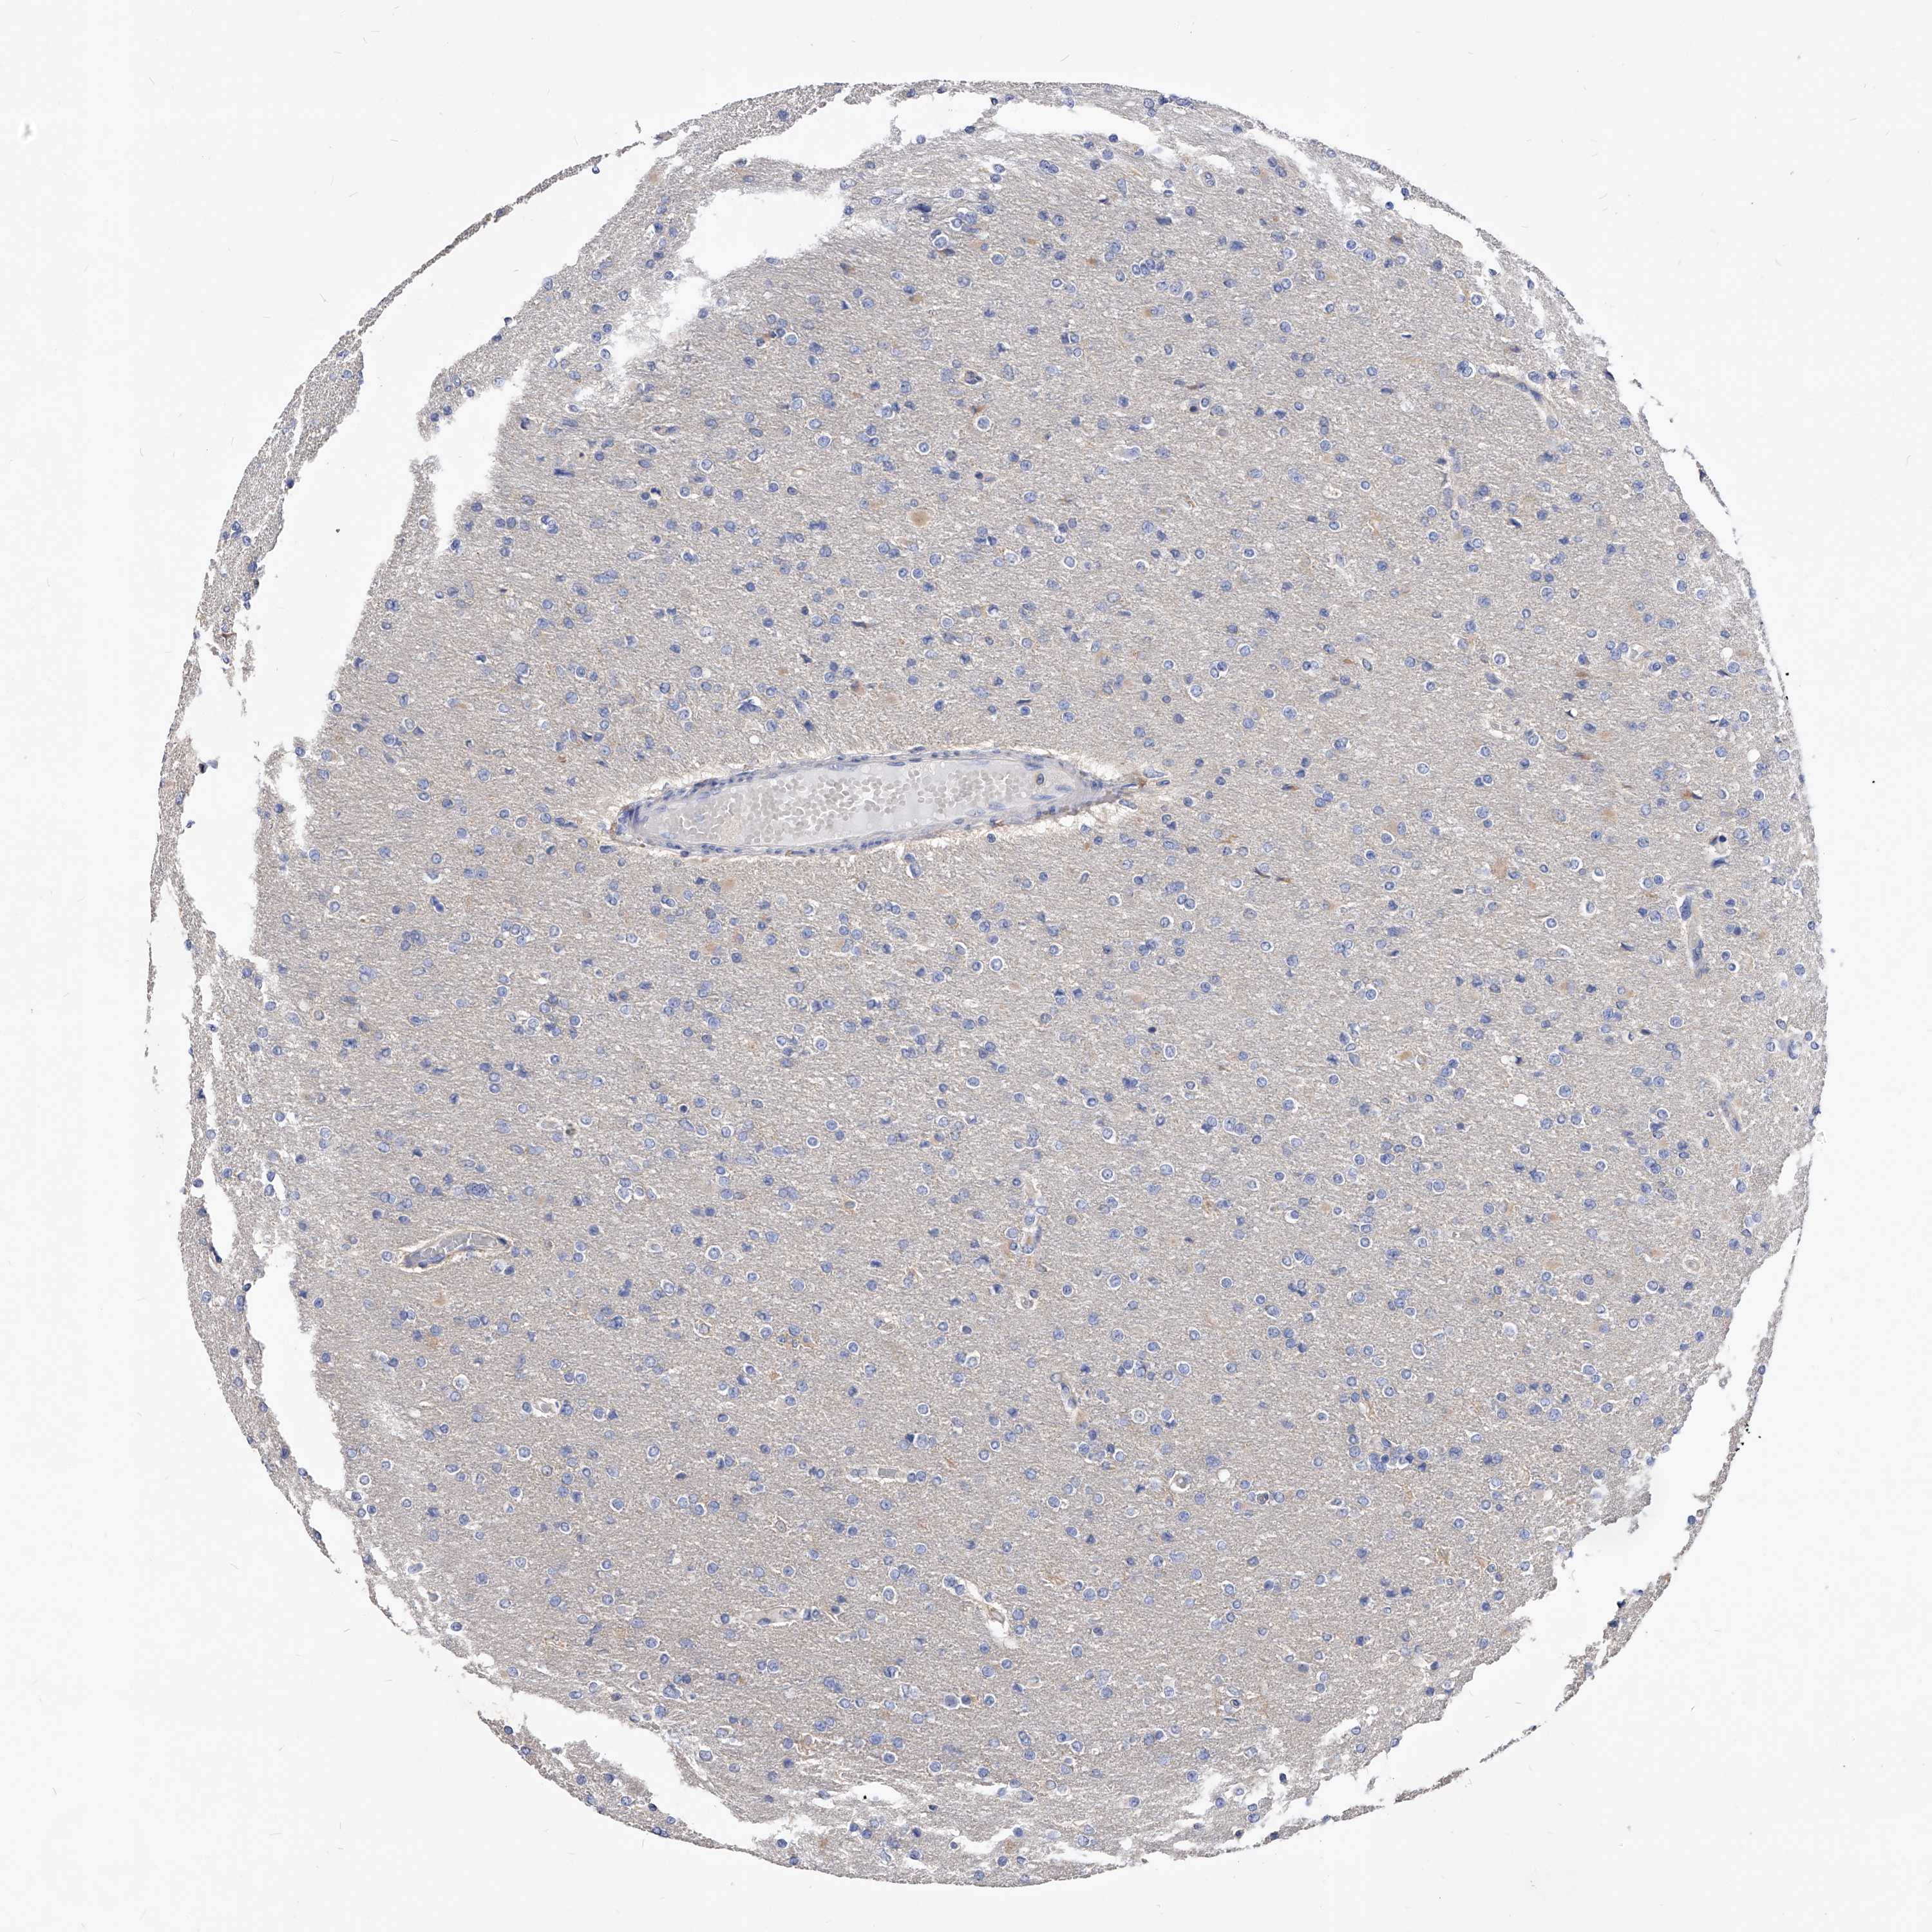

GLIOMA - Protein expressioni

A mouse-over function shows sample information and annotation data. Click on an image to view it in a full screen mode. Samples can be filtered based on level of antibody staining by selecting one or several of the following categories: high, medium, low and not detected. The assay and annotation is described here.

Note that samples used for immunohistochemistry by the Human Protein Atlas do not correspond to samples in the TCGA dataset.

Antibody stainingi

Antibody staining in the annotated cell types in the current human tissue is reported as not detected, low, medium, or high, based on conventional immunohistochemistry profiling in selected tissues. This score is based on the combination of the staining intensity and fraction of stained cells.

Each image is clickable and will lead to virtual microscopy that enables deeper exploration of all samples and also displays staining intensity scores, fraction scores and subcellular localization as well as patient and tissue information for each sample.

Antibody HPA029700

Antibody HPA029701

Antibody HPA029702

Antibody HPA029703

Staining

High

Medium

Low

Not detected

Intensity

Strong

Moderate

Weak

Negative

Quantity

>75%

75%-25%

<25%

None

Location

Nuclear

Cytoplasmic/membranous

Cytoplasmic/membranous,nuclear

Glioma, malignant, High grade

Glioma, malignant, Low grade

Glioblastoma, NOS